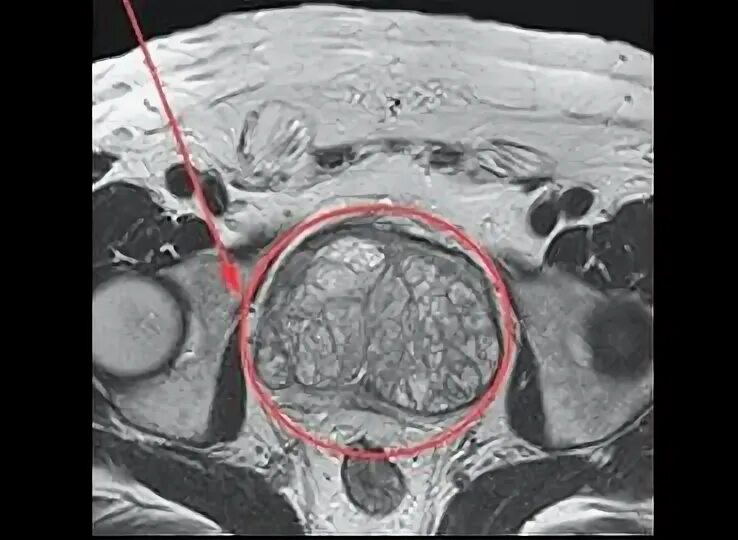

Перед мрт простаты